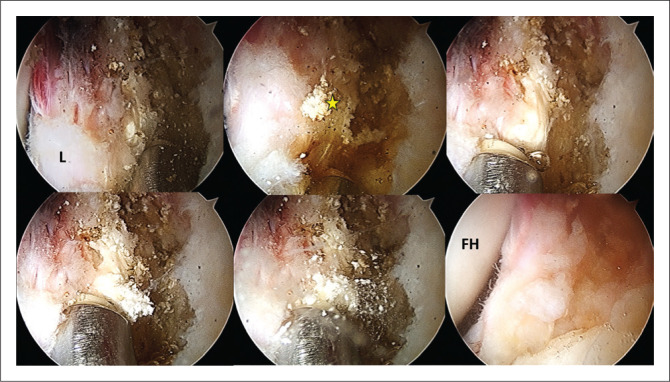

This report describes a rare case in which double calcifications of the acetabular labrum and rectus femoris occurred concomitantly in a middle-aged female patient who was treated successfully with surgical intervention via hip arthroscopy.

Contribution: This case highlights the existence of various types of calcifications around the acetabulum, with a proposed new classification system for acetabular and periacetabular rim ossifications.